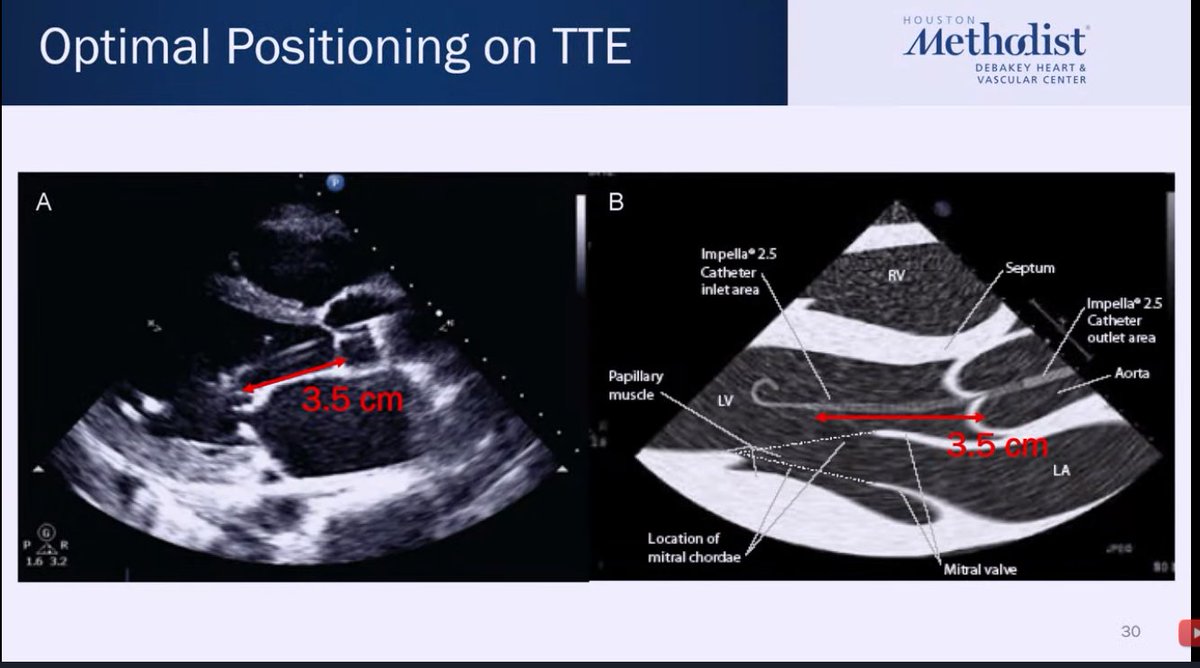

Pure 🦪for first year fellows from @IceTeaMD re: temporary MCS! ✔️placement of IABP Impella! ➡️Top right: waveforms when Impella is in aorta, push Impella in. ⬅️Bottom left: waveforms when Impella is in LV, pull Impella out. 💡How to reposition w TTE guidance. #CVBootCamp2021

HJRyooAli's tweet image. Pure 🦪for first year fellows from @IceTeaMD re: temporary MCS!

✔️placement of IABP Impella!

➡️Top right: waveforms when Impella is in aorta, push Impella in.

⬅️Bottom left: waveforms when Impella is in LV, pull Impella out.

💡How to reposition w TTE guidance.

#CVBootCamp2021